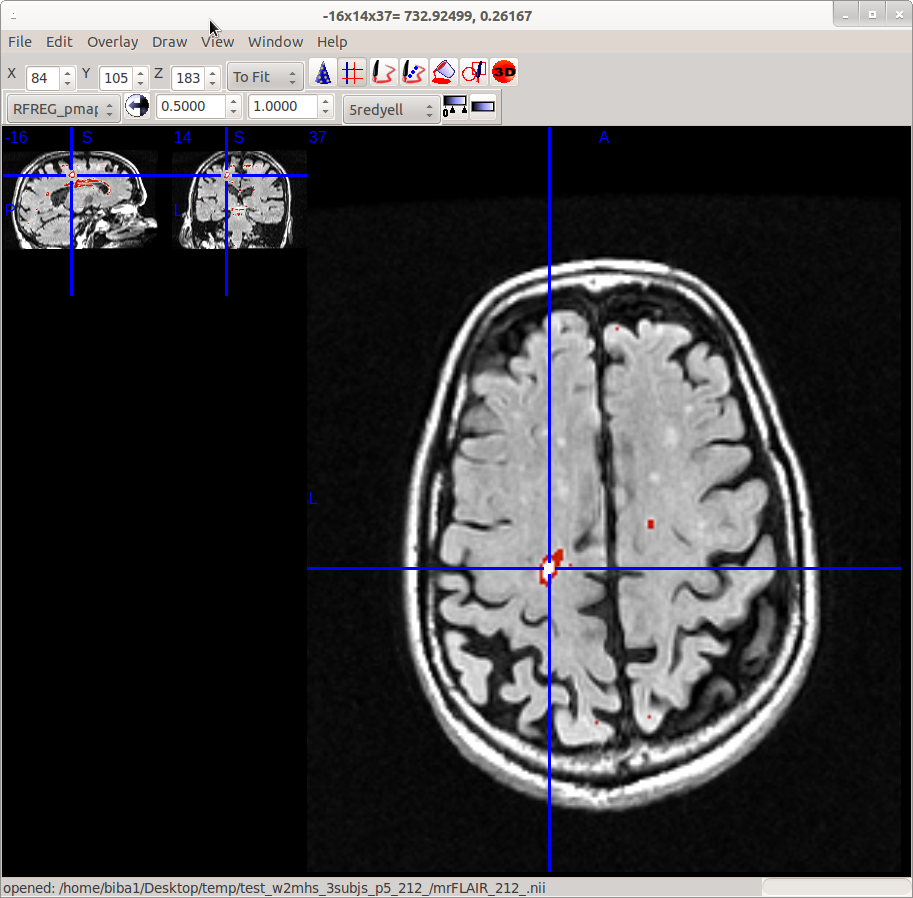

I wanted to chime in on this conversation and post a picture depicting the issues that we are having as well.

The image is of the T2 registered to the T1 and overlayed with the pmap displayed at a .5 to 1 threshold. This test subject was pre-processed through the W2MHS program and had the default, 2.5 cleaning threshold as well. You can see from the attached image that the program is identifying major hyperintensities (although not some of the smaller ones in this particular slice), but more importantly, is missing the center of the hyperintensities. The probability for the voxels along the edge of that hyperintensity are slightly above .5, while the voxels in the center are around .2.

Therefore, we would be interested in the features and training codes as well. Any thoughts on this issue are greatly appreciated.